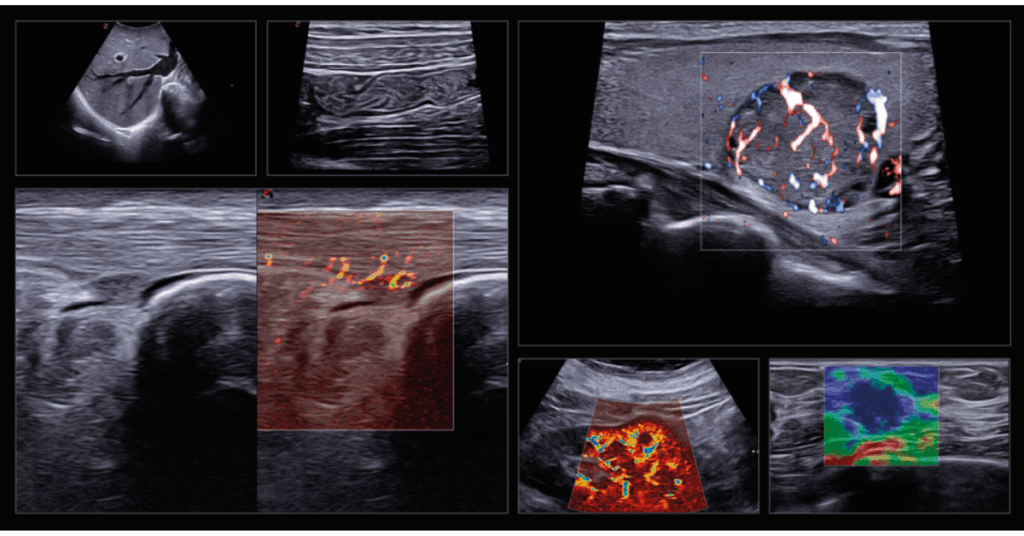

Komplexní řešení umožňuje detekci, sledování a léčbu širokého spektra onemocnění – od hepatologie a urologie, přes radiologii, gastroenterologii, gynekologii až po sportovní medicínu. Technologie, jako fúzní zobrazování (US-MRI), Virtual Navigator nebo UroFusion, podporované umělou inteligencí, poskytují přesné vedení intervencí a cílených biopsií v reálném čase.

Díky funkcím jako BreastNav™MRI, QPack, QElaXto 2D či Single Crystal sondám nabízí MyLab™X9 dokonalé zobrazení měkkých tkání, vaskularizace i strukturálních detailů s frekvencí až 25 MHz.